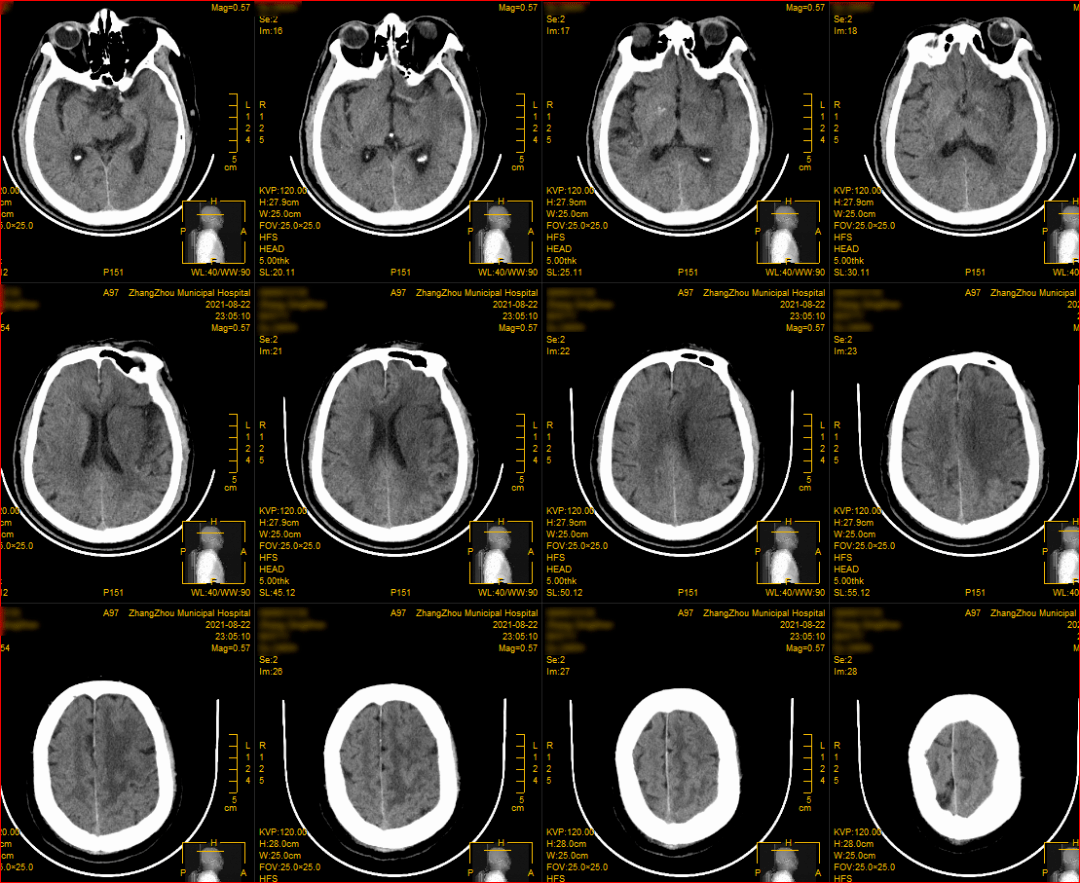

术前头部cta示大脑中动脉走形分支区域见增粗动脉血管影,局部呈结节状

(术前颅脑cta)